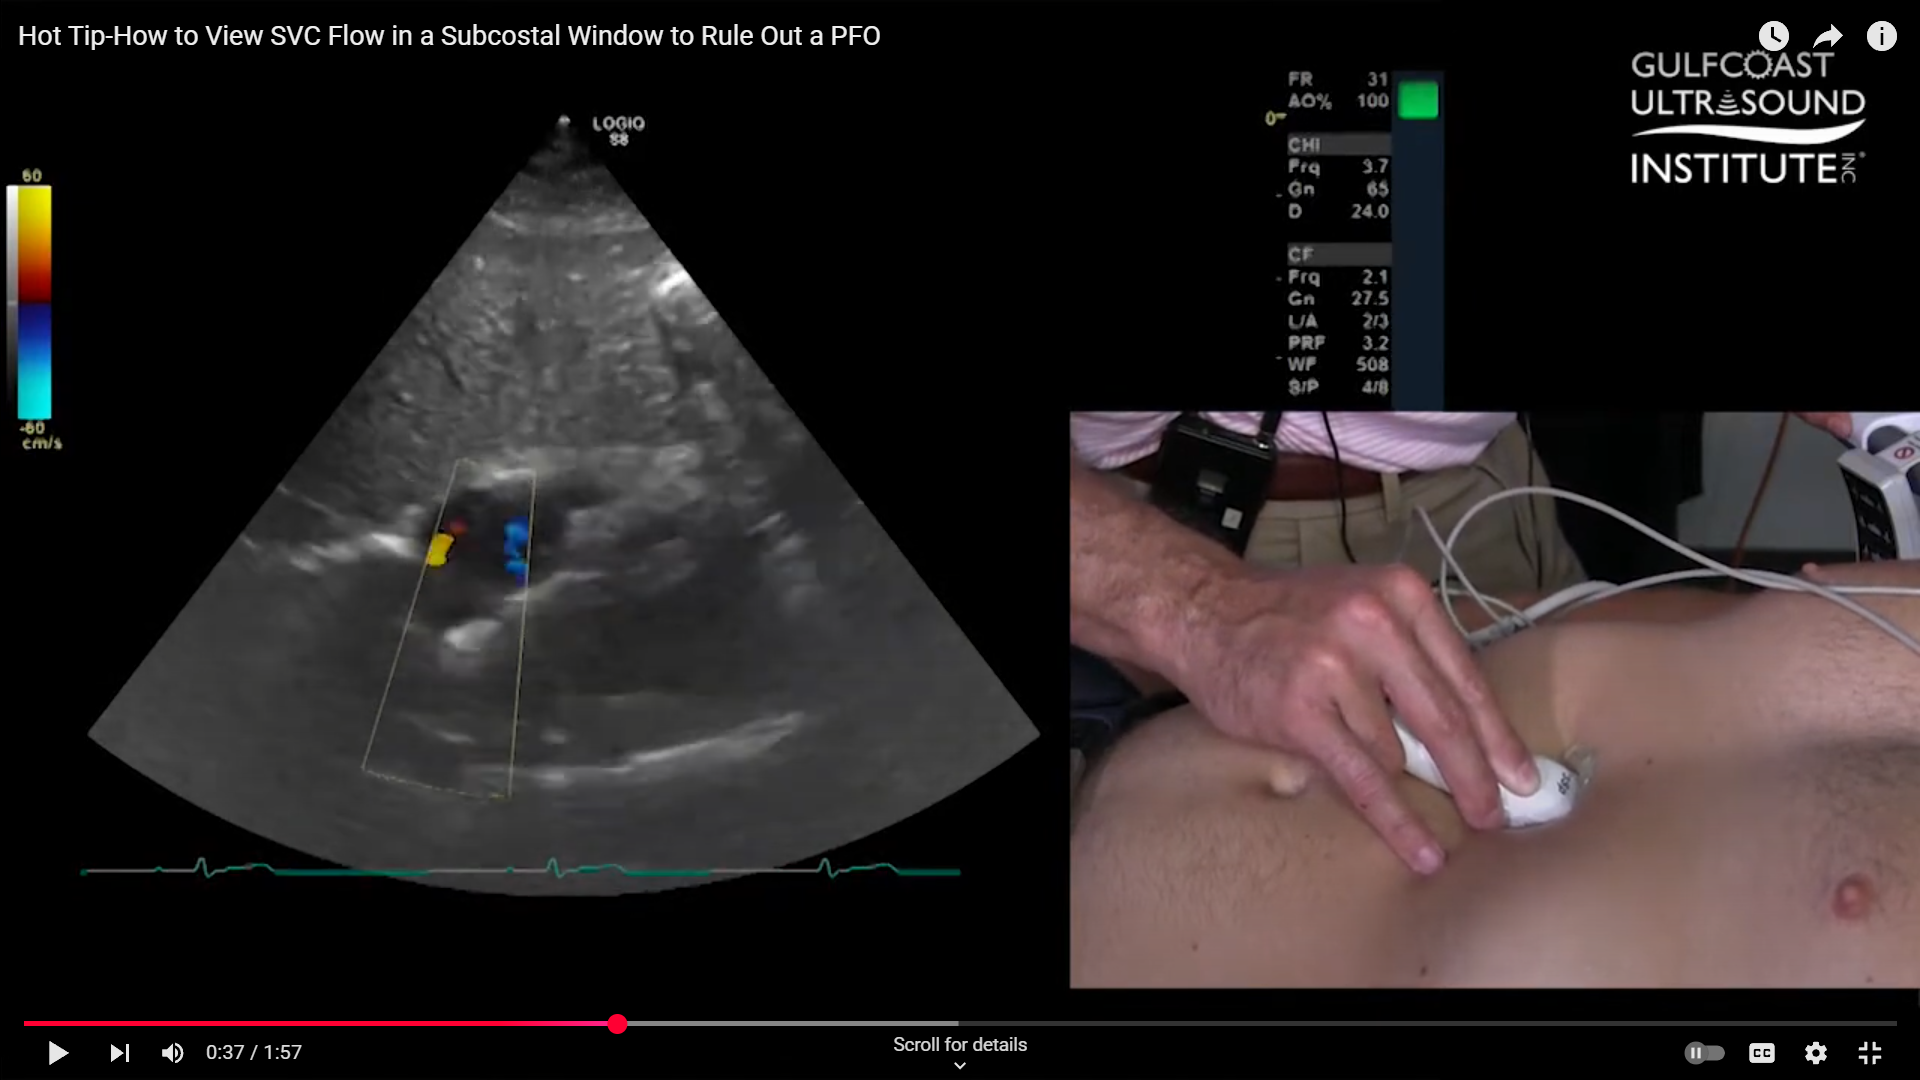

Applying Color Flow Doppler

Once you’ve identified the SVC, applying color flow Doppler can help visualize the blood flow pattern. Normally, you’ll see red laminar flow moving into the right atrium. However, distinguishing between this normal SVC flow and a PFO shunt can be challenging. Sometimes, the color Doppler image isn’t clear enough to show whether there’s a true PFO or just normal flow dynamics.

The Key Adjustment for Better Imaging

Here’s where a small adjustment can make a big difference. From your standard three o’clock view of the subcostal window, rotate your probe toward the five o’clock position. By making this shift, you bring the bicaval view into focus, allowing you to see both the inferior vena cava (IVC) and SVC together. On your screen, you’ll notice the SVC flow coming up and curving slightly to the right.